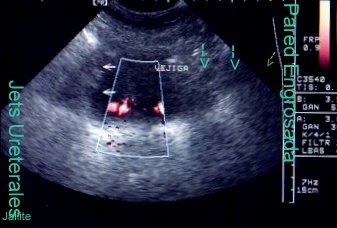

- Ecografía pelviana.